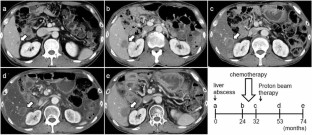

We report a case of a male in his 50 s who underwent pancreaticoduodenectomy for solid pseudopapillary neoplasm (SPN) of the pancreas at 30 years. He developed a liver abscess 15 years after the surgery, and CT scan revealed a swollen retroperitoneum lymph node and a tumor in the liver. Symptoms, including abdominal distension, appetite loss, and epigastric pain, appeared due to lymph node metastasis. Endoscopic ultrasonography-guided fine-needle aspiration against the lymph node revealed SPN recurrence. The tumor had invaded the common hepatic artery, and surgery was not indicated. Chemotherapy of Gemcitabine/nab-Paclitaxel biweekly was performed 8 times; however, no reduction in tumor size was observed, and the patient’s symptoms worsened. Proton beam therapy (67.5 GyE in 25 fractions) was subsequently performed for lymph node metastasis, and led to a gradual reduction in lymph node metastasis, and an improvement in symptoms. No re-expansion of lymph node metastasis has been observed 3 years after proton beam therapy. Since SPN is low malignancy and most cases can be expected to be cured by surgery, there is currently no standard treatment of unresectable SPN. This case is the first report of proton beam therapy for SPN, and was considered to be effective.